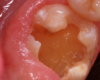

A 9-year-old boy had a partially erupted mandibular first molar with much hypocalcification of the occlusal surface and a large caries lesion involving the occlusal and buccal surfaces (Figure 1). The patient complained of continuing sensitivity to cold stimulus and air inspiration. Because the tooth was only partially erupted, consideration for stainless steel crown full coverage had to be delayed. As an interim repair, it was decided to debride the carious tooth substance and place a light-hardened calcium silicate/mineral trioxide aggregate (MTA) liner, followed by a bonded restoration. After inferior alveolar block anesthetic injection and cotton roll isolation, cavity outline form was cut using a high-speed, water-cooled, medium-grit cylindrical diamond bur (Figure 2). Insufficient eruption precluded use of a rubber dam. A large, round bur at slow speed was used to debride the carious enamel and dentin. The prepared surfaces were swabbed for two 60-second applications of a 5% glutaraldehyde/HEMA solution for desensitization and disinfection of the preparation.6,7 Cavity liner was then injected and spread over the deepest sections of the cavity floor and hardened with the visible light beam (Figure 3). After a self-etching bonding agent was applied over the remaining enamel surfaces, without the need for any type of matrix, an RMGI bioactive ionic resin-based composite was injected, in one portion, into the preparation and spread over the four cusps using a ball burnisher. This restorative complex was then photo-polymerized using two 20-second exposures of the visible light beam (1,200 mW/cm2). The restoration was trimmed and finished with large, round diamond burs at slow speed, and occlusion was evaluated with articulating paper and adjusted.

A 9-year-old presented with hypoplasia, hypocalcification, and caries.

Figure 1